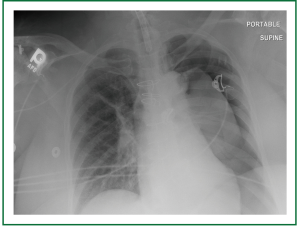

Supportive measures were immediately undertaken with multiple intravenous vasoactive medications, and blood pressure ultimately responded only to escalating doses of epinephrine and an epinephrine infusion. Given the above measurements and patient’s medical history, a cardiac event was considered most likely, but a jet ventilator associated complication could not be ruled out so no repeated attempts were made at jet ventilation. Due to the fact that the trachea was at this time fully exposed, the decision was made to insert the tracheostomy. Incision was made in the trachea and trachesotomy was inserted without incident. Upon arrival to the ICU, the patient continued to have hypotension. Decreased breath sounds were suspected on the left. A chest x-ray shot immediately after this finding confirmed large left-sided tension pneumothorax with mediastinal shift and evidence of left heart compression (Figure 3). A chest tube was introduced immediately relieving a large volume of air and allowing the weaning of the epinephrine infusion, with complete liberation of the infusion by post-operative day two. The patient was eventually deemed medically stable for transfer to a skilled nursing facility, after prolonged hospitalization, with a functional tracheostomy airway and nutrition with gastrostomy tube feeds.